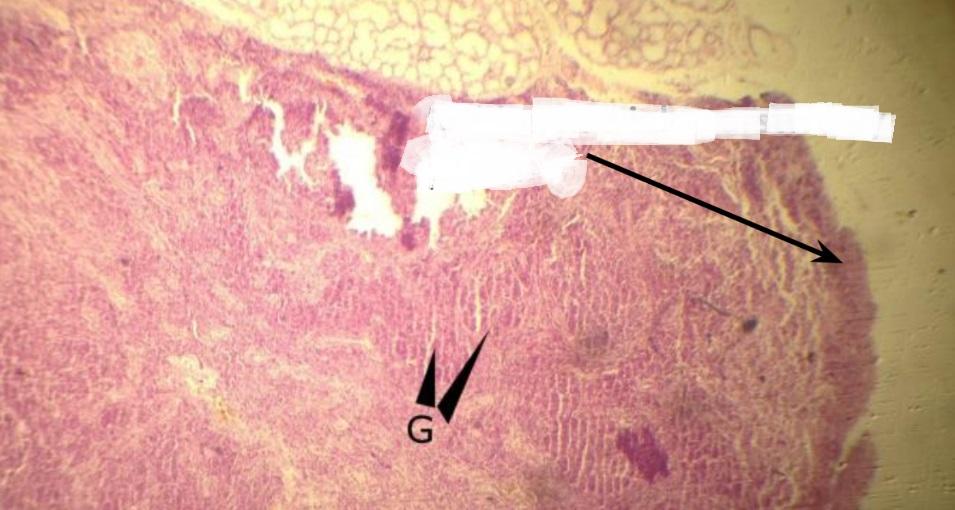

Pytanie 113

zatoka brzeżna (śledziona)

Pytanie 114

zatoka właściwa (śledziona)